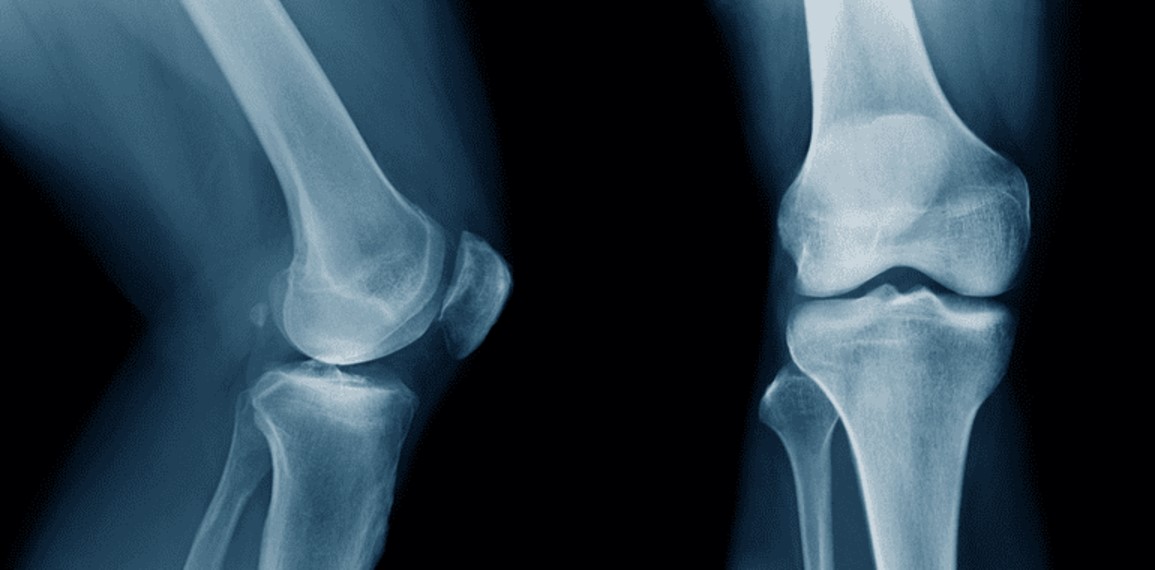

Researchers in China have developed a groundbreaking bio-adhesive known as Bone-02, capable of repairing fractures in just three minutes. This innovative product, which biodegrades as the bone heals, could transform the approach to fracture treatment, eliminating the need for traditional metal plates and screws.

Crafted by a team at Zhejiang University School of Medicine and Xiaoshan Hospital, Bone-02 is inspired by the natural adhesive properties of oysters. After nearly a decade of research, the team, led by Professor Pan Xunwu, has created a material that not only effectively binds bone fragments but also dissolves within six months, significantly reducing the need for secondary surgeries.

Clinical trials involving over 150 patients have showcased the adhesive’s efficacy. For instance, a patient with a comminuted wrist fracture had their bone fragments securely fixed through a small incision measuring just 2–3 cm. In contrast, conventional treatments would typically necessitate a larger incision and a second surgery approximately a year later. After a recovery period of three months, the patient’s wrist function was fully restored without complications.

The adhesive exhibits impressive metrics, with a tensile strength of over 181 kg, a compressive strength of approximately 10 MPa, and a shear strength of around 0.5 MPa. These figures suggest that Bone-02 may become a formidable competitor to existing surgical materials, as noted by Global Times.